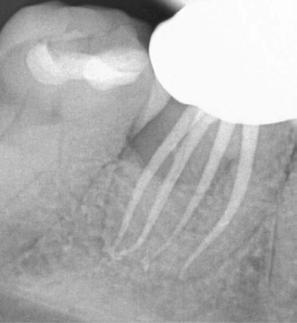

Figure 4 (left): Preoperative image of tooth No. 15. Figure 5 (right): Postoperative image. Rotary negotiation with Roto-reciprocation in all 3 canals with lengths from 25-28 mm and the ProTaper Ultimate Slider advanced to WL within 2 passes